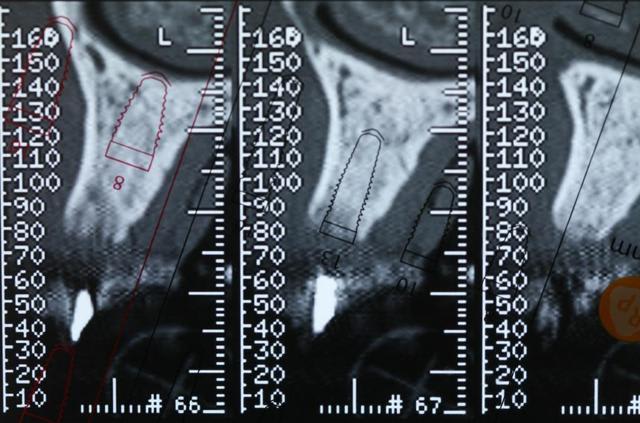

Bon voila le scann de 11-12 (pas 21-22 comme noté)

C'est vrai que j'ai à mort d'os en épaisseur.

Le manque est surtout en hauteur.

Dans tous les cas je refais 21 en même temps.

Tu ne ferais qu'un conjonctif enfoui ? Tu crois que c'est fiable dans le temps ?

tu exagères, 4-5 mm en hauteur pour quoi faire pxav ?

regarde les photos et la ligne des collets

j'ai l'impression qu'il ne manque pas d'os en verticale, ou à peine en 12.

Un bon cj avec un lambeau décalé en palatin ou en rouleau pour gagner en épaisseur me semblerai suffisant

le montage guide RX laisse supposer un manque d'un mm en 12 et ok en 11. Surcomble en cj pour en éliminer au cas où avant les empreintes